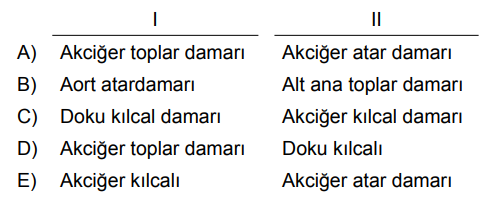

Soru 2 |

İnsan akciğerinde bulunan bazı yapılar numaralar ile gösterilmiştir.

Buna göre, aşağıdakilerden hangisinde numaralı kısım ve ismi yanlış eşleştirilmiştir?

1 → Soluk borusu | |

2 → Bronş | |

3 → alveo | |

4 → bronşcuk | |

5 → periost zarı |